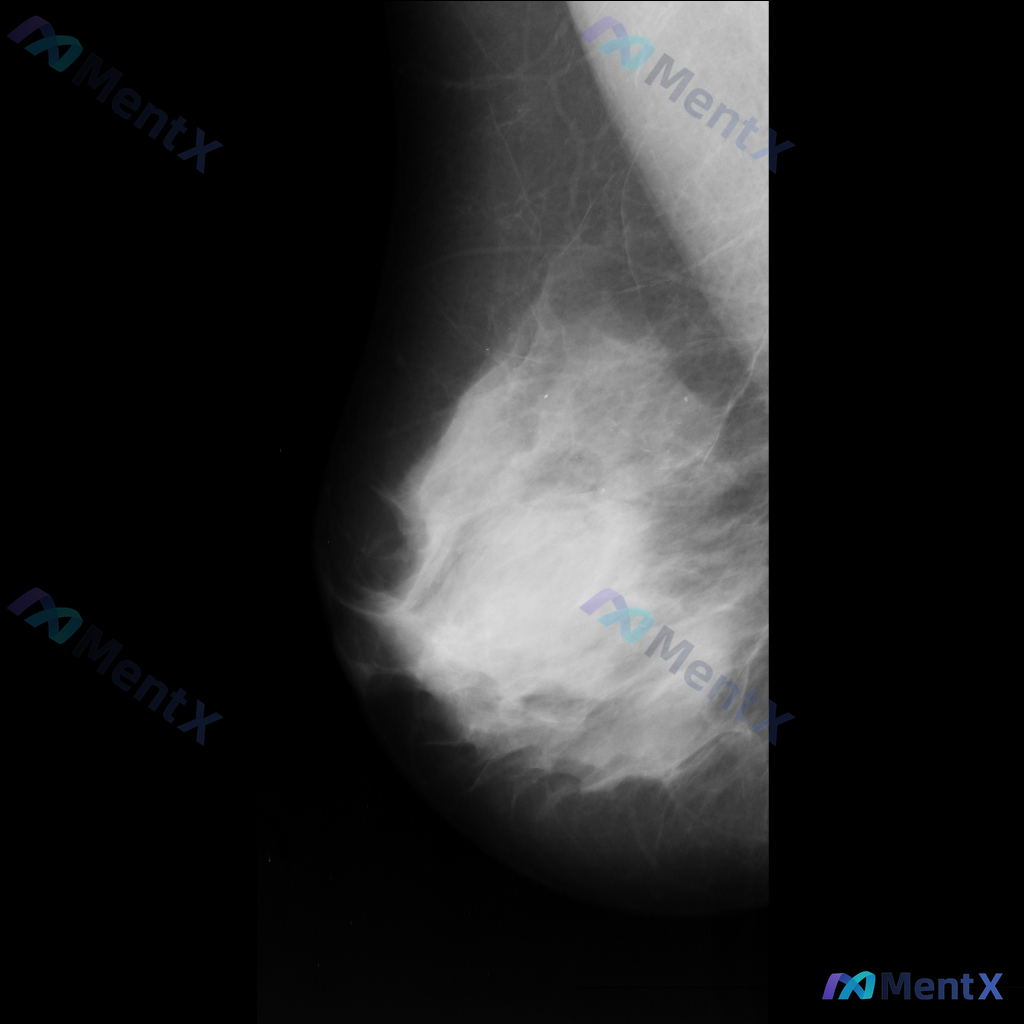

整理了一张乳腺钼靶影像的讨论资料,先和大家分享一下读片描述: 影像可见:不规则、高密度肿块/不对称致密影,伴有毛刺状边缘、结构扭曲和散在钙化。 目前考虑可能存在几种不同的异常方向,想先听听大家的第一反应——单看这组影像特征,你会先往哪种情况考虑? 也可以说说你最关注的是哪一点表现。

整理到一张乳腺钼靶影像的分析资料,先和大家同步一下核心表现: - 乳腺构成:不均匀致密型 - 主要异常:在乳腺中央偏上区域可见一个不规则形高密度肿块,边缘有毛刺样改变;围绕这个高密度影,周围的乳腺小叶和导管结构紊乱,向病灶中心牵拉。 目前暂时没有更多临床病史、查体或其他检查补充。想先问一下大家:单看...

整理到一组乳腺钼靶的影像资料,大家先一起看看: 影像表现: - 病灶位于乳腺上中部(大致外上象限)可见一局限性高密度肿块影 - 形态不规则,边缘有毛刺状改变 - 周围腺体结构有扭曲、牵拉征象 - 肿块内部或附近可见点状钙化,部分呈簇状分布 目前只有这组钼靶表现,大家先不补充更多临床信息的话,大家更倾...